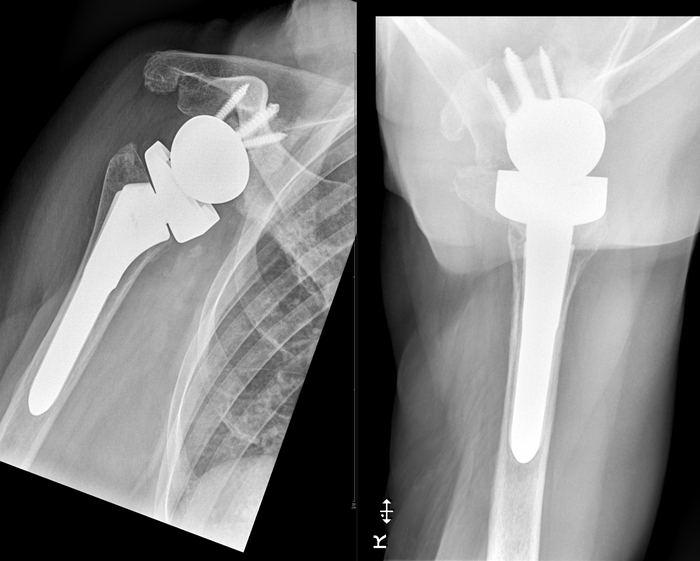

Начнём с нижних конечностей, где импланируют протезы:

- тазобедренных суставов

вплоть до полного протезирования бедренной кости

- коленных суставов (как частичное, так и тотальное эндопротезирование)

Перейдём к верхней конечности, где имплантируют протезы:

- плечевых суставов

- локтевого сустава (как частично, так и тотально)

1/2